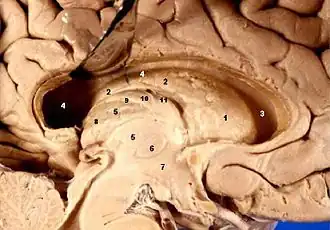

Cross-section of the monkey hypothalamus displays two of the major hypothalamic nuclei on either side of the fluid-filled third ventricle. - Hypothalamic nuclei